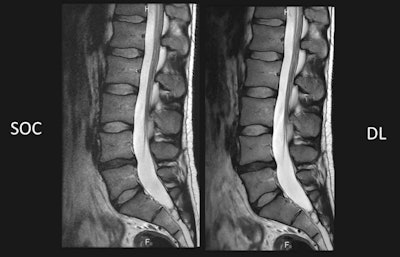

Comparison of standard of care (SOC) against deep learning-based (DL) reconstruction at 60% shorter scan time. Images courtesy of Dr. Lawrence Tanenbaum.In addition to these cross-sectional models that analyzed each data point separately, the researchers tested their second hypothesis by developing longitudinal models that treated a patient's sequence of DEXA scans as a single data point.